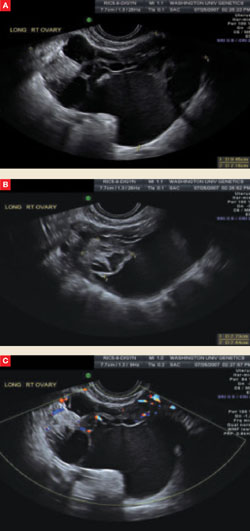

FIGURE The complex nature of a mass comes to light via ultrasonography

This complex mass of the right ovary, seen from different vantage points in A and B, contains multiple cysts and septations. Minimal blood flow is apparent in C.